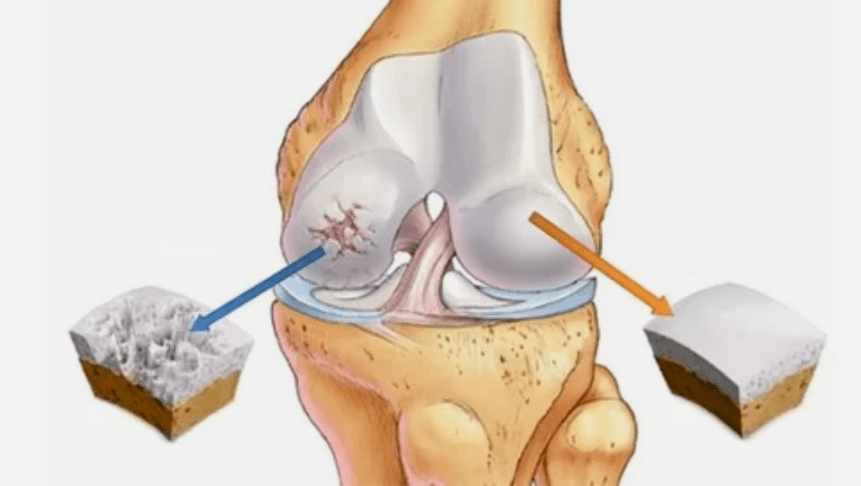

- Hüalini kattepatoloogiad. Kõhre hõrenemine viib selle patoloogiliste kudede - luustruktuuride - asendamiseni.

- Anomaalsed kasvud esinevad kõhredel - osteofüütidel.

- Kõhre ja luude loodusliku anatoomia tekkimine kutsub esile kõhre tervislike alade ülekoormuse. Artikli kudede hävitamine ravimata progresseerub pidevalt ja põhjustab puudeid.

Kui haiguse aste suureneb, on patoloogilised protsessid endiselt süvenenud. Lõpuks hävitatakse kogu Hyalini kõhre.